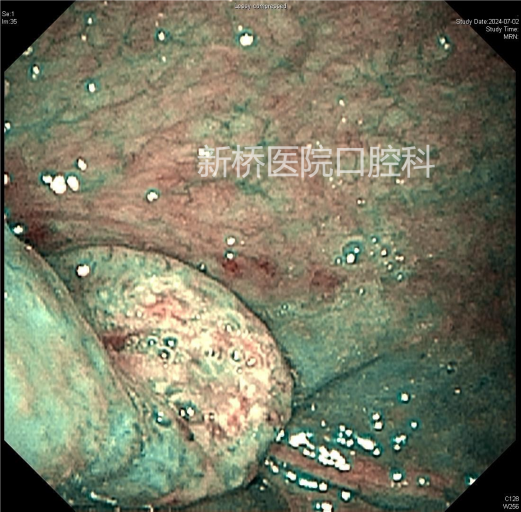

经口腔治疗口咽部、喉部、甚至咽下部区域的手术,因解剖结构复杂、视野严重受限,临床上操作难度极大。经口机器人手术(Transoral robotic surgeryTORS)是经口腔手术技术上的革新,属于内镜经口腔手术的一种。其利用带角度镜头臂伸入口内,使得上述部位放大的3D影像完整呈现于术者眼前,获得视野更宽广,更清晰,更逼真的深部